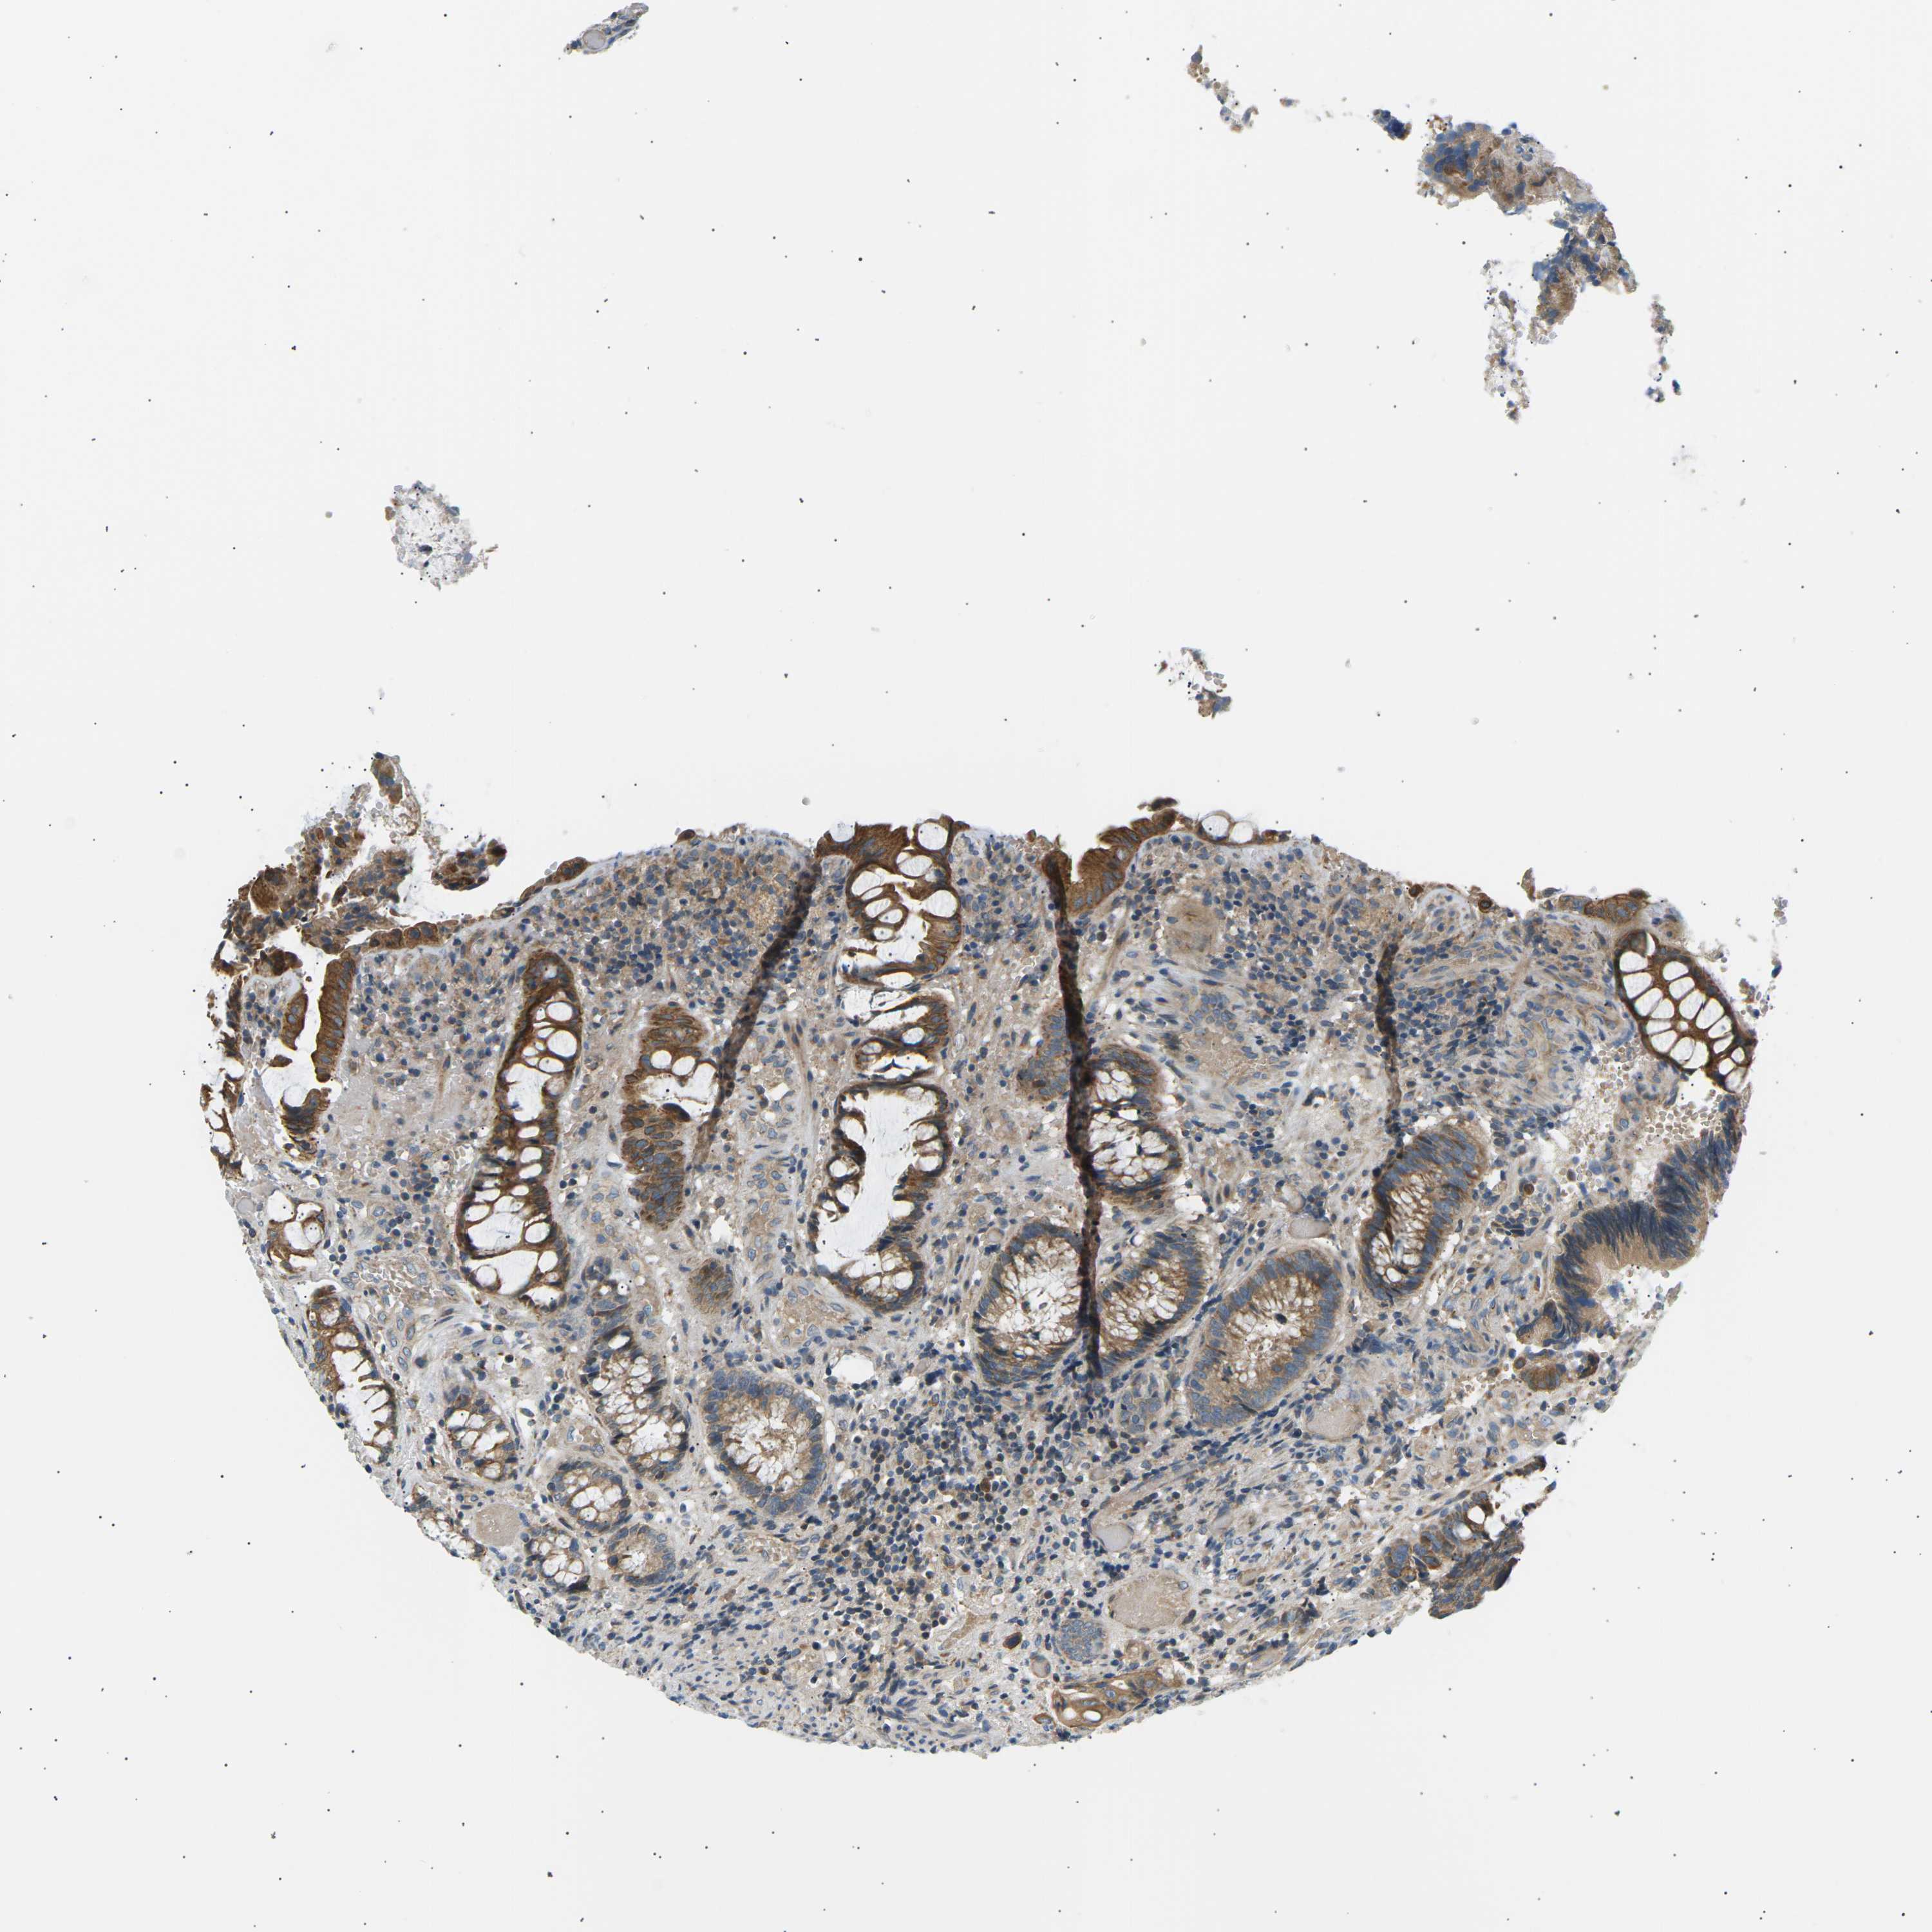

CANCER COLORECTAL CANCER Show tissue menu

Colorectal cancer

Human cancer

Colon adenocarcinoma